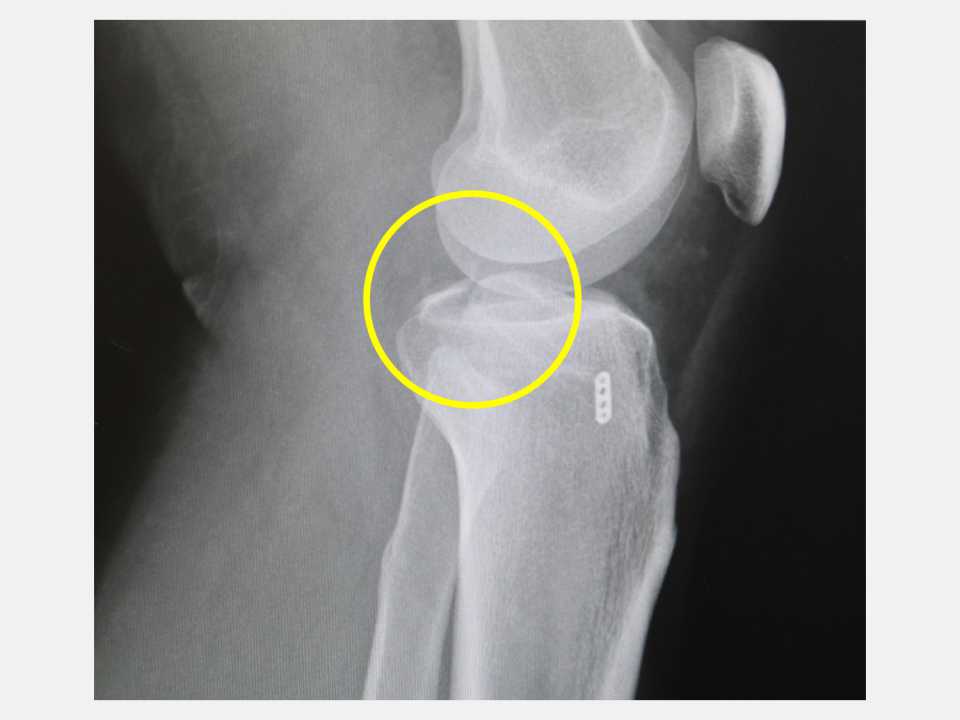

【記者 韓佩穎 台中報導】台中一位28歲黃先生在騎機車上班途中發生車禍,左腳膝蓋又腫又痛,不只躺在地上爬不起來,甚至連膝蓋彎曲都有困難,由救護車送到仁愛長庚合作聯盟醫院(大里仁愛醫院)的急診室,X光檢查發現其左腳膝關節骨折,經進一步電腦斷層掃描後顯示是脛骨後十字韌帶撕脫性骨折(posterior cruciate ligament avulsion fracture)。運動醫學中心徐振恆醫師安排微創關節鏡輔助復位固定手術後,黃先生隔天就開始下床走路,並進行復健運動,2個月之後已經回到正常生活。

徐振恆醫師指出,由於台灣機車族眾多,每天交通事故頻繁,除了常見擦傷、骨折外,膝關節的十字韌帶受傷也屢見不鮮。黃先生的後十字韌帶撕脫性骨折(即後十字韌帶連帶一小塊骨折塊從脛骨上被拉起),最常見於機車車禍,原因是在跌倒時膝蓋彎曲脛骨受到直接向後的衝擊力所造成。黃先生在事故發生後膝蓋不但疼痛、腫脹,還感覺膝蓋不穩,即使勉強拿拐杖行走,膝關節也沒有力氣支撐,這種傷勢不但可能造成膝關節不穩,若未即時和正確治療,還可能導致日後膝關節退化與功能障礙。